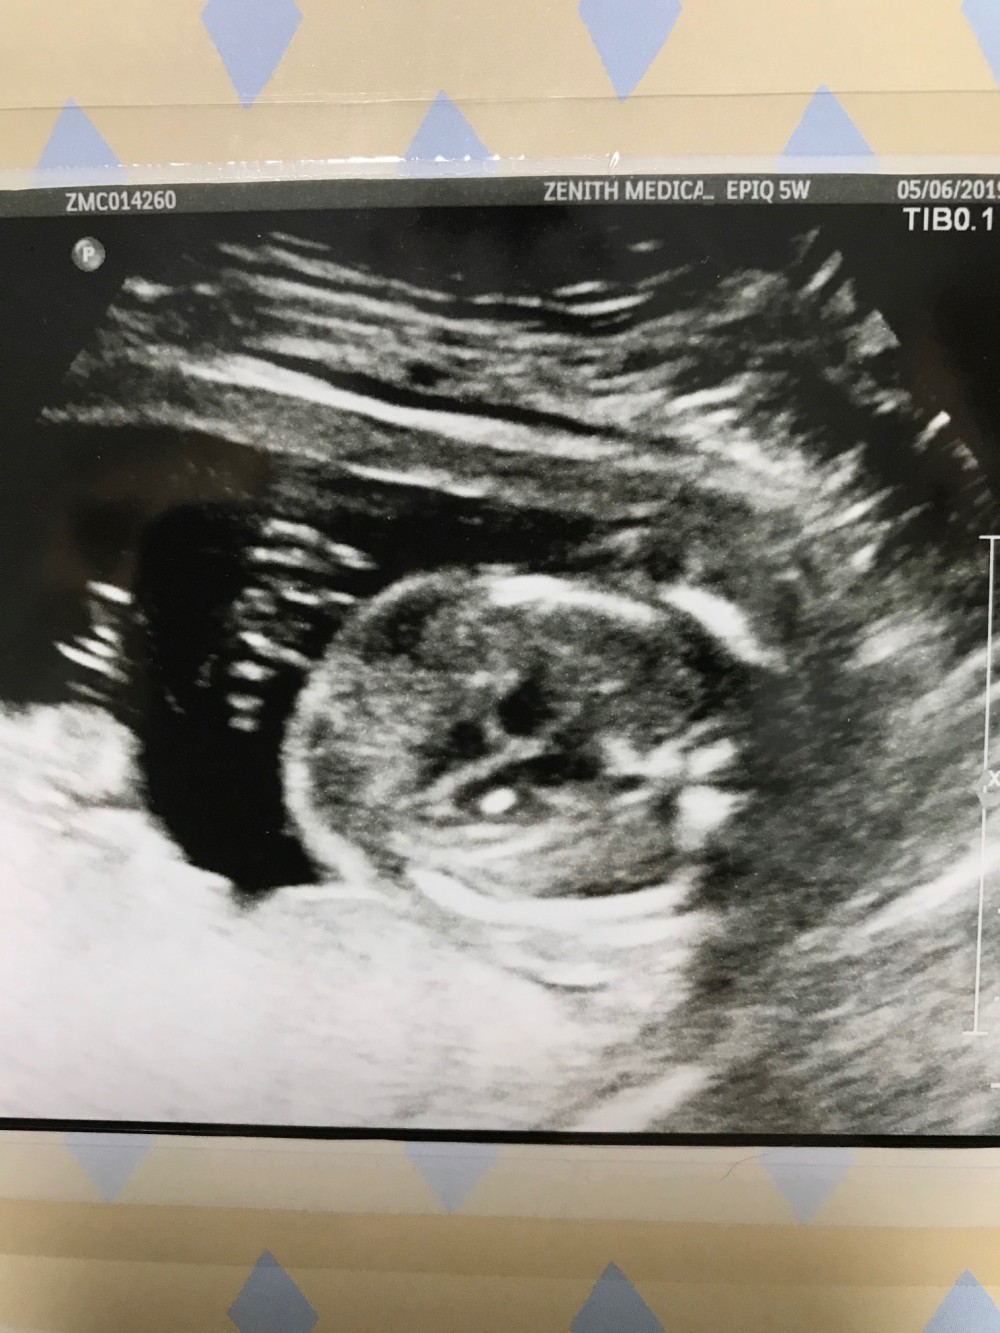

醫生一直也沒有提及弟弟條腸,我跟老公也差不多忍耐不住要問,然後他就說有兩件事要留意,一是弟弟心臟有光點;二是腸也有光,心臟的光點我是能看到啦因為真的很光和蠻大點的,但是腸那邊我跟老公都完全看不懂,加上又沒有比較,所以我們也沒有辦法知道有多光,醫生也沒說,他只是說因為有抽nifty所以應該不是唐寶寶,但因為有兩樣懷疑的地方所以還是寫轉介信讓我去政府再照。因為也是有心理準備,所以我跟老公也沒問多少就出去等信。然後!到姑娘叫我付錢的時候,只是把報告給我及問我收錢,我說那轉介信呢?她完全是什麼都不知道的樣子,還跟我說醫生沒寫也走了因為要接生!我其實很不理解,一來已經擔心只想快點到政府排期;二來外面姑娘不知道就算了,跟症姑娘也沒打算管嗎?然後姑娘說叫我先走等醫生下午四時回來再叫他寫及whatsapp給我,我反駁政府接受whatsapp的轉介信嗎?姑娘回答那我就不清楚了。啊!這是有多不負責任?最後我中午照完,在附近等至四時再回去等醫生寫信,五時半才把信給我,只好明天才抽時間到威院排期⋯⋯唉!